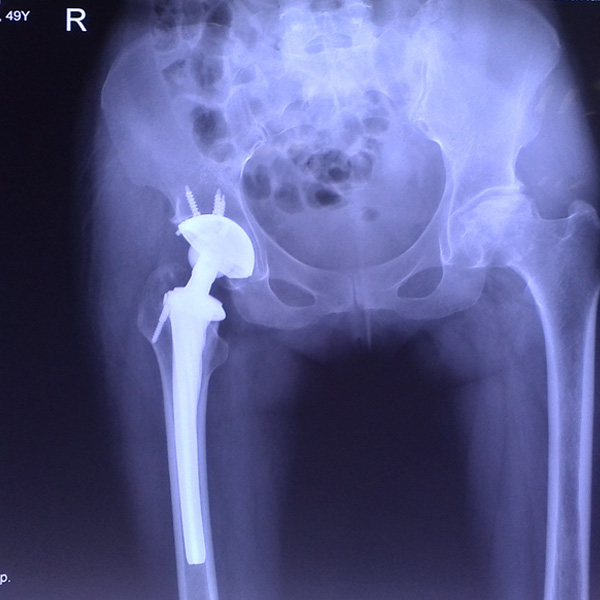

髖關節(jié)翻修

患者蘇某,女性,11年前因“左髖關節(jié)屈曲攣縮畸形”行左側人工全髖關節(jié)置換,近來感覺左髖關節(jié)疼痛,不敢行走,經(jīng)“攜生醫(yī)療平臺”就診于哈......